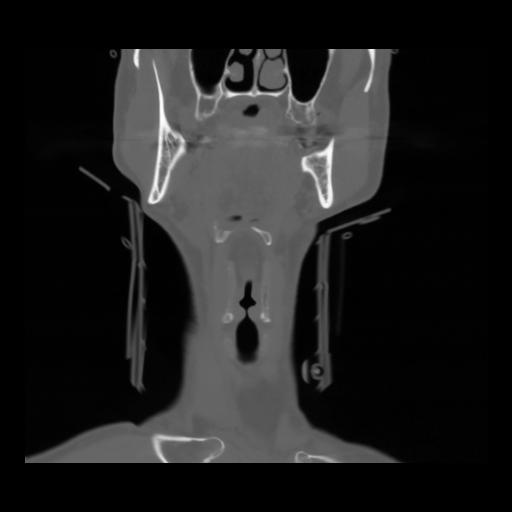

13 P.BLANDAS,,Coronal,2.000,P.BLANDAS,Coronal,